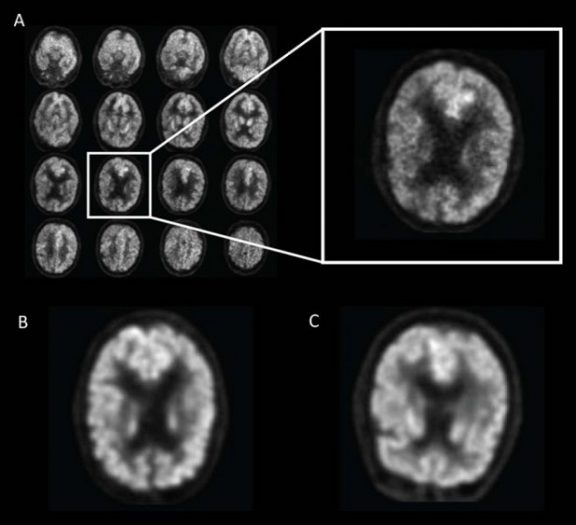

یکی از ابزارهایی که در حال حاضر برای تشخیص آغاز آلزایمر کاربرد دارد، نوعی اسکن مغزی موسوم به “پت‌اسکن” (PET scan) است. در گذشته از این روش برای شناسایی انواع سرطان استفاده می‌شد اما در سال‌های اخیر، کارآیی آن در تشخیص آلزایمر نیز اثبات شده است.

به گزارش نوروسافاری از انجمن رادیولوژی امریکای شمالی، پژوهشگران “کالج دانشگاهی لندن” (UCL) در این بررسی جدید، یک الگوریتم یادگیری ماشین را برای ارزیابی اسکن‌ها آموزش دادند. “جائه هو سون” (Jae Ho Sohn)، از نویسندگان این پژوهش گفت: فناوری یادگیری عمیق می‌تواند الگوهای فرعی بیشتری را در داده‌های تصویربرداری نشان دهد. تفاوت در الگوی جذب گلوکز در مغز، بسیار ظریف و پویا است. یافتن زیست‌نشانگرهای مربوط به بیماری، کار ساده‌ای است اما تغییرات متابولیک می‌توانند فرآیند جامع‌تری ارائه دهند.

پژوهشگران، این الگوریتم را روی مجموعه‌ای از اسکن‌های مغزی مورد بررسی قرار دادند و الگوریتم توانست همه موارد موثر بر پیشرفت آلزایمر را تشخیص دهد. از این نظر، الگوریتم به طور قابل توجهی از رادیولوژیست‌های انسانی، برتر بود.